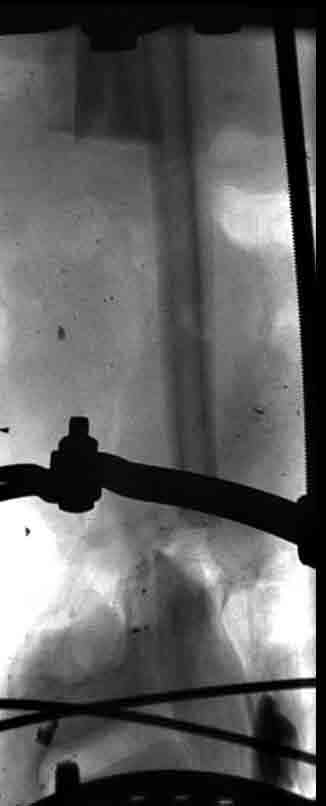

5. Ну и чтобы не быть голословным. Молодой человек подорвался на фугасе (Чечня, 2005 год). Свежие рентгенограммы:

Соответственно ожоги и дефект мягких тканей, переломы костей стопы и пр. Наложили аппарат

Илизарова (как придется), хирургически обработали и героически заживляли мягкие ткани с многочисленными кожными пластиками. В итоге через полгода я принял его вот таким:

Реализовал описанную выше методику, и в итоге вот что получилось. Высылаю лишь прямые проекции,

в боковых тоже всё в тему.

Очень пригодились карбоновые кольца (Джолдас -огромное спасибо, я твой должник!!!), поскольку остеопороз дистального отломка был просто невероятный. На цифровом рентгене с трудом угадывались контуры.

Рентген в процессе перемещения - внизу карбоновые кольца, тракция фрагмента спицами с упором.

внешний вид в аппарате - не завершающем этапе, сначала стопа тоже была фиксирована в аппарате.

Сейчас аппарат сняли, но случай ещё не завершенный.

Признаюсь честно, не совсем уверен в прочности консолидации на стыке косточек. Кроме того, укорочение в районе 6 см. Сейчас реабилитация - ходит опираясь на ногу с одним костылем.

Продолжение, видимо, будет... Возможно, будем удлинять.